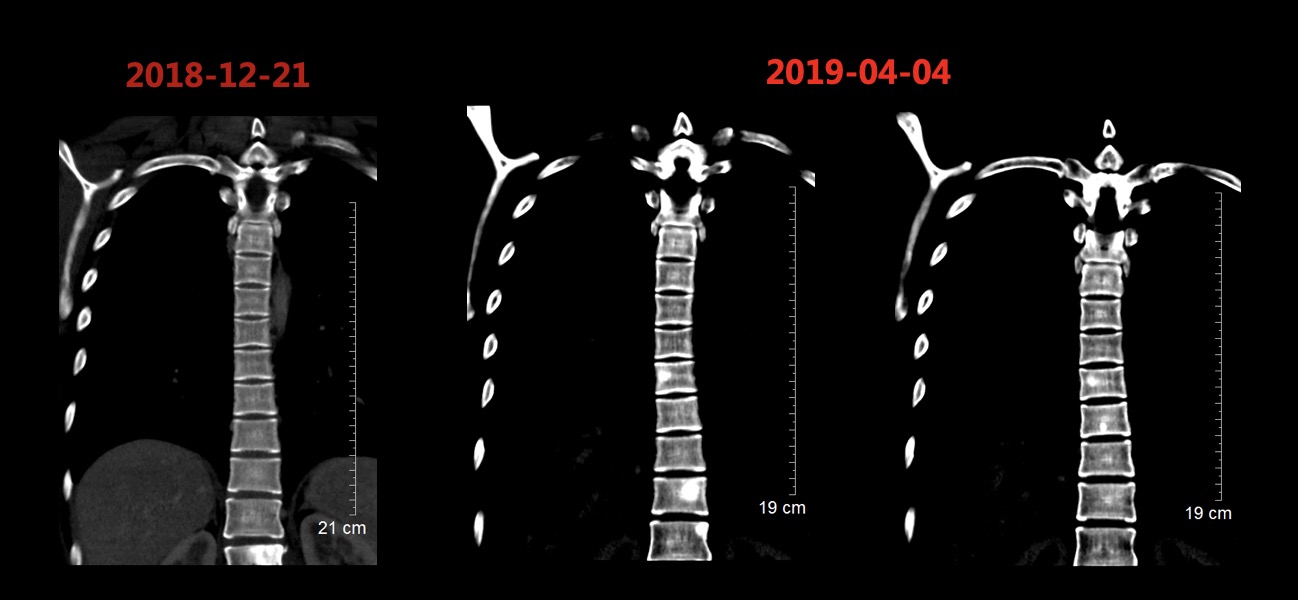

2019-02-19、2019-03-14行二线贝伐珠单抗+多西他赛化疗(贝伐珠单抗+多西他赛,每3周1次)。2019-03患者开始出现腰部疼痛,考虑为L1椎体骨转移导致,2019-03-19开始行腰骶部局部放疗,2019-04-04复查CT结果如图5所示,肺部病灶稳定(部分缩小),肝脏病灶增多增大、T9-T12椎体新发转移瘤,总体疗效评价(PD)。

image011.jpg

图5 2019-04-04复查胸腹部CT结果影像,结果显示肺部病灶稳定(部分缩小),肝脏病灶增多增大、T9-T12椎体新发转移瘤